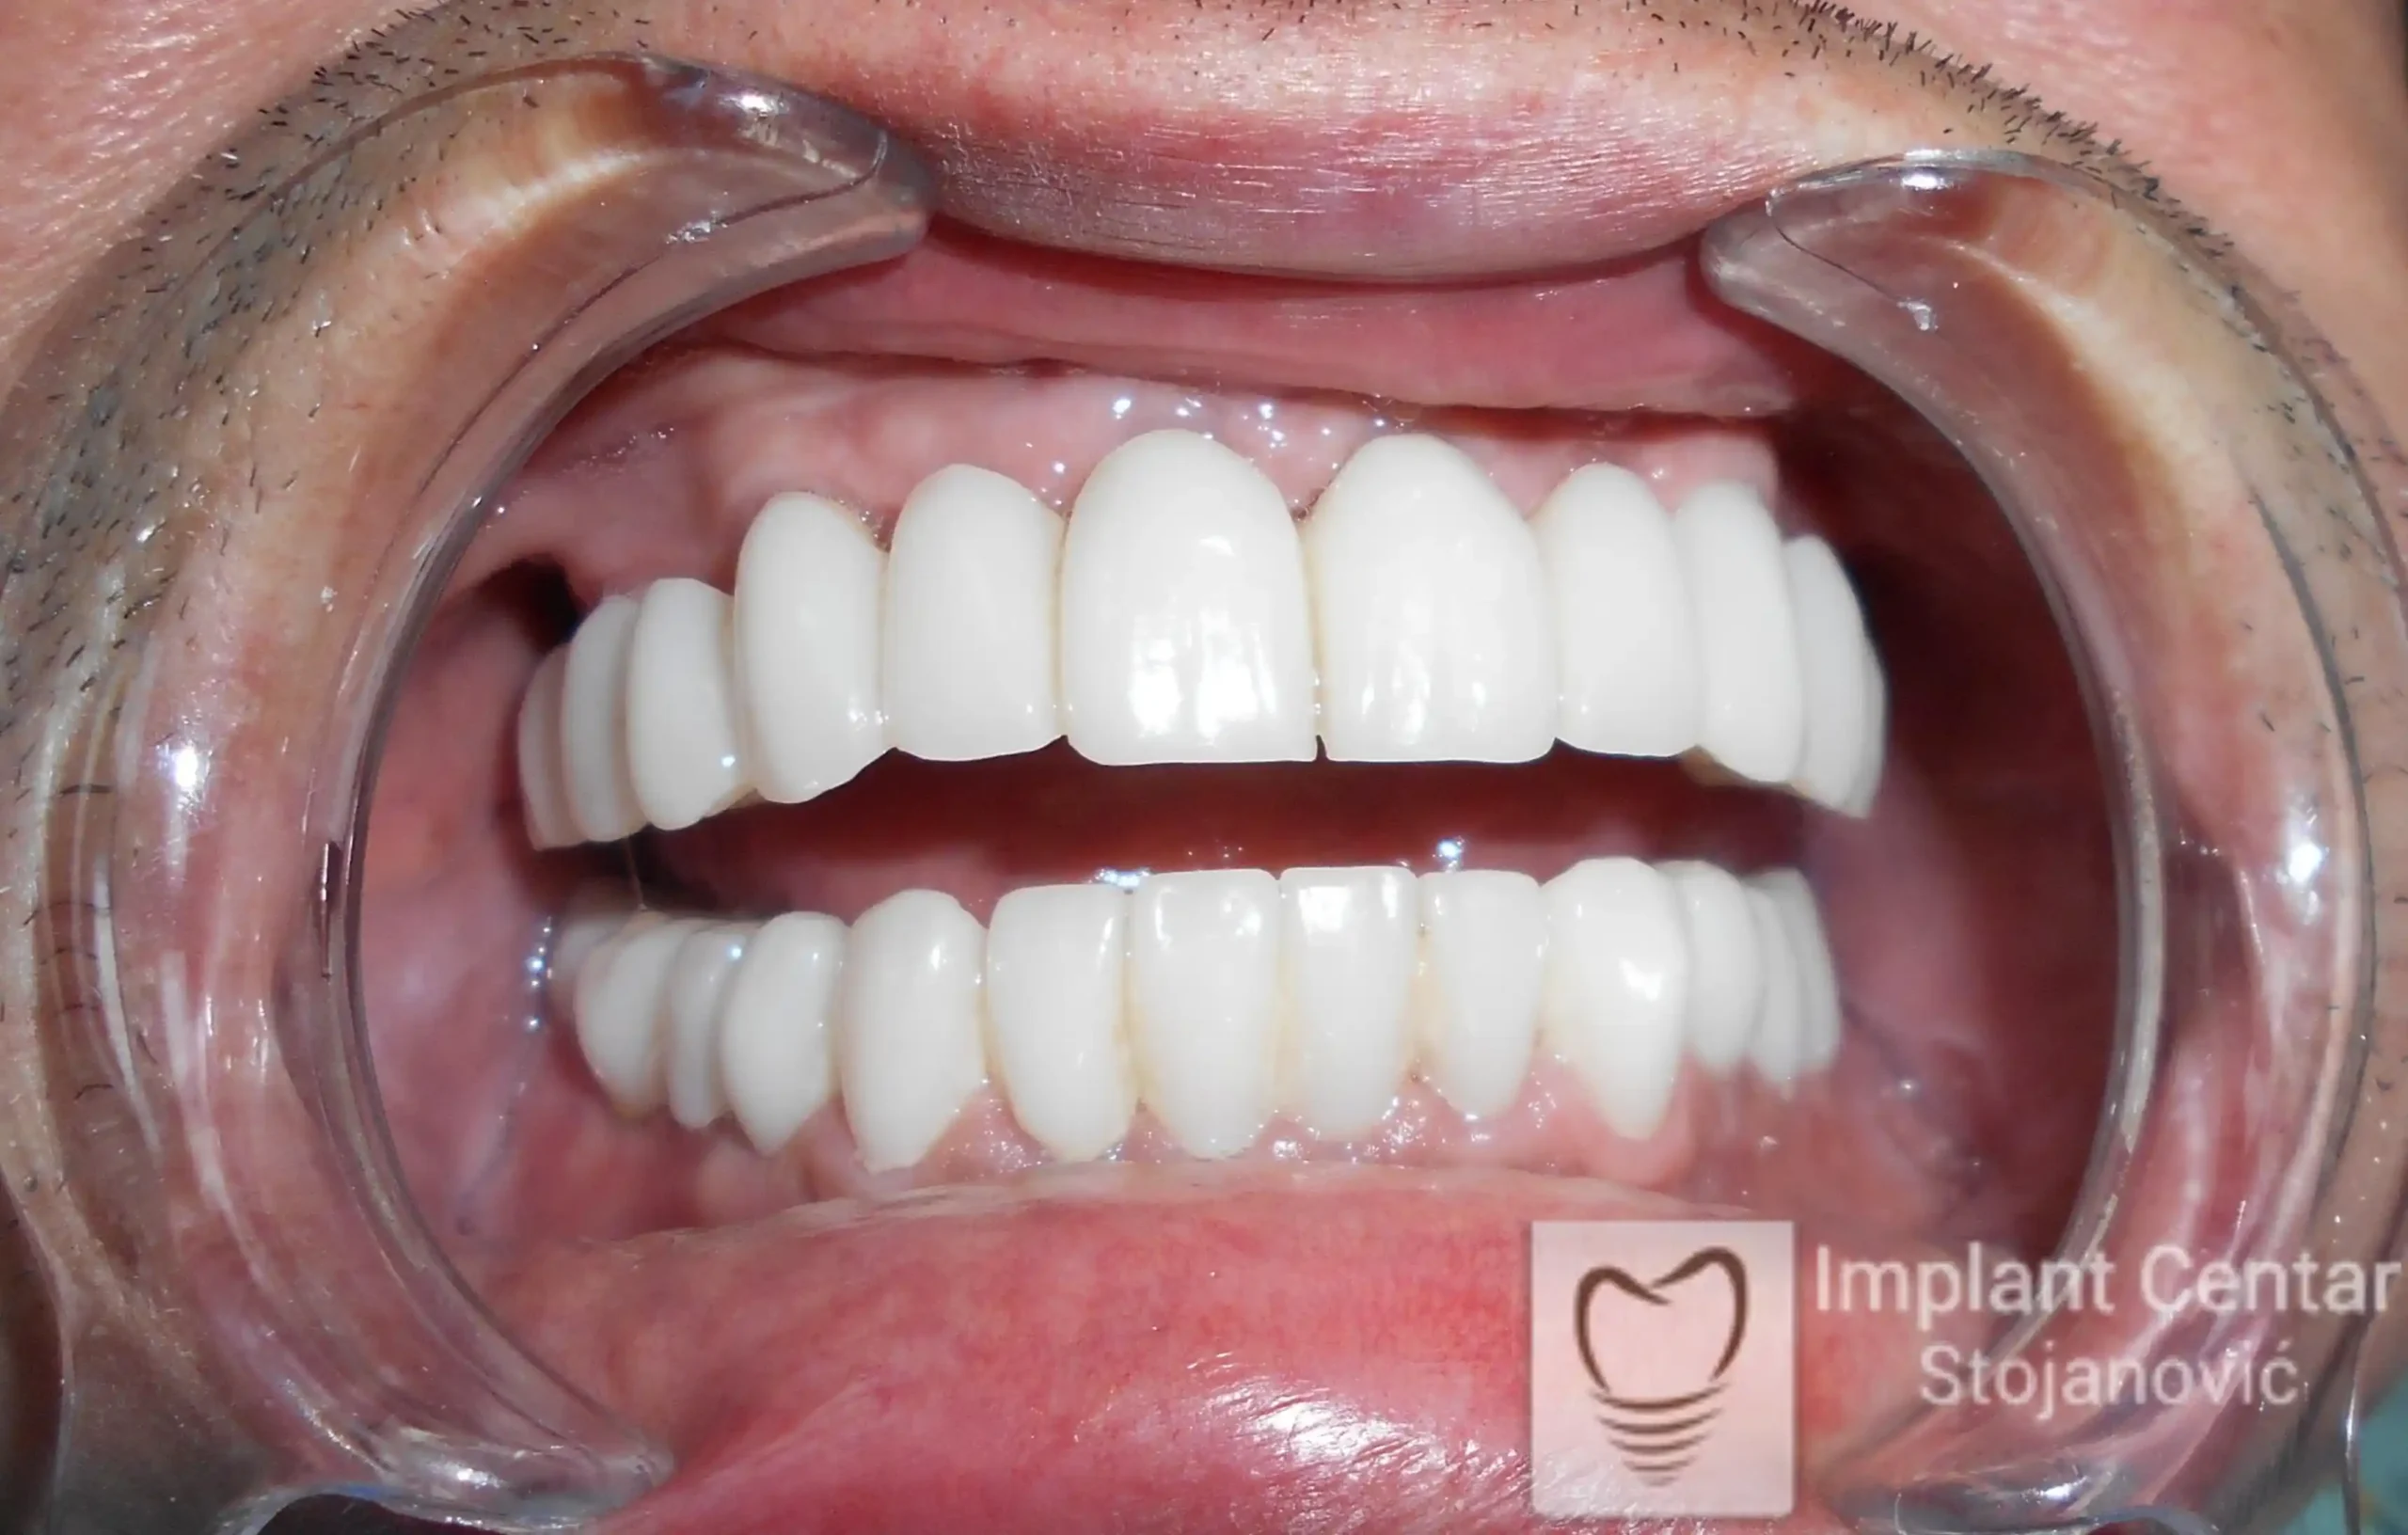

Na slikama 1 i 2 prikazan je klinički izgled pacijenta pre početka terapije. Nakon detaljnog kliničkog pregleda, analize radioloških snimaka, kao i razgovora sa pacijentom o njegovim željama i očekivanjima, izrađen je sveobuhvatan plan terapije. Terapija je podrazumevala vađenje preostalih zuba, ugradnju dentalnih implantata i izradu fiksnog protetskog rada na implantatima.

Tokom perioda osteointegracije, pacijent je bio zbrinut fiksnim privremenim krunicama na implantatima, čime su očuvani estetika i funkcija. Nakon završetka perioda integracije, izrađeni su definitivni cirkonijum-keramički mostovi (slika 6 i 7 ).